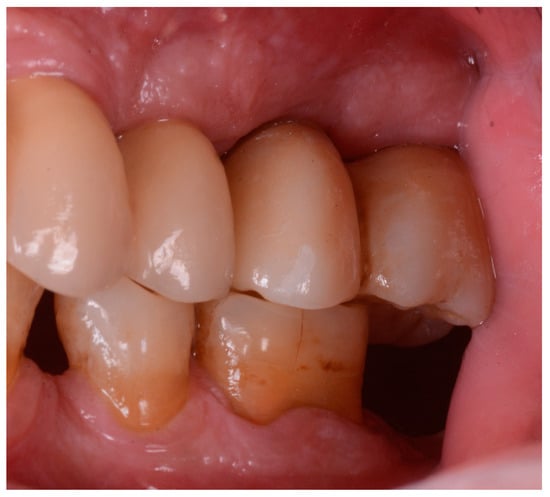

Figure 2 and Figure 3 illustrate the case conclusion, featuring an X-ray of the prosthetic rehabilitation after the extraction of the implant and neighboring teeth, along with an image of the completed prosthesis.

Figure 2.

X-ray after the implant retrieval and rehabilitation restoration.

Figure 3.

Clinical observation after implant retrieval and rehabilitative restoration.